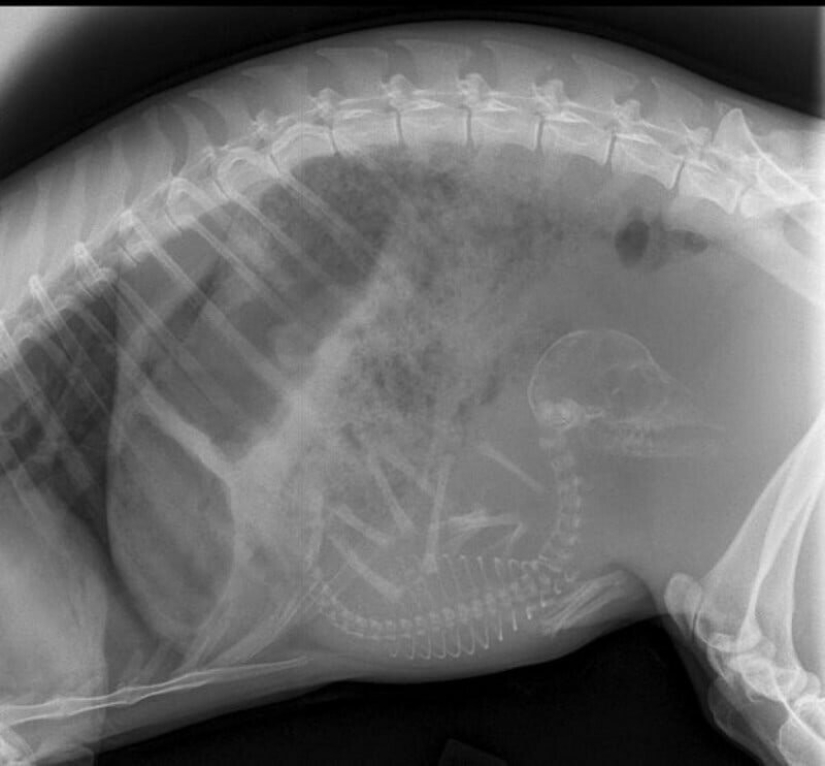

Pregnant doe